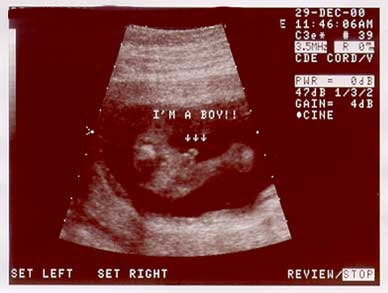

These images show the baby at 17wks. (Dec. 29, 2000) |